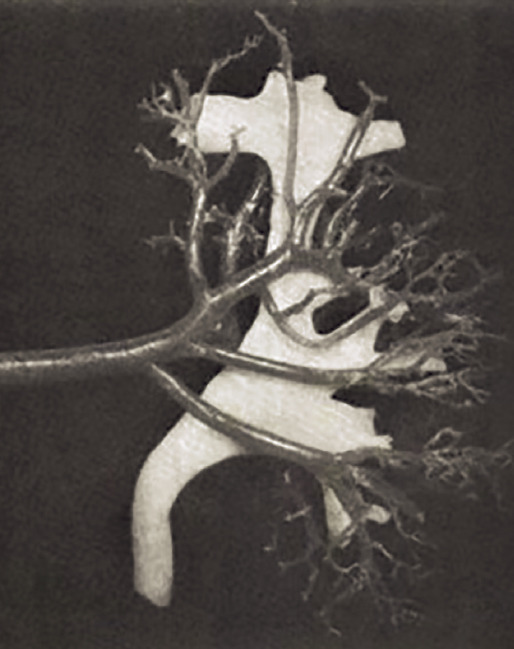

The aim of the present paper is to contribute to the understanding of the history of the anatomical study of the intra-renal arteries. The vasculature and especially the intra-renal arteries of the kidneys are an intriguing field which was first studied through art and then perfected by medicine. Angiography and microsurgery have resulted in partial nephrectomy techniques for surviving kidneys with adequate functional results. Graves' categorization dating from 1954 opened the way for innovative approaches that have resulted in modern topographical anatomy. CONCLUSION: Our understanding of the anatomy of intra-renal arteries has played a significant role in surgical anatomy and internal medicine.